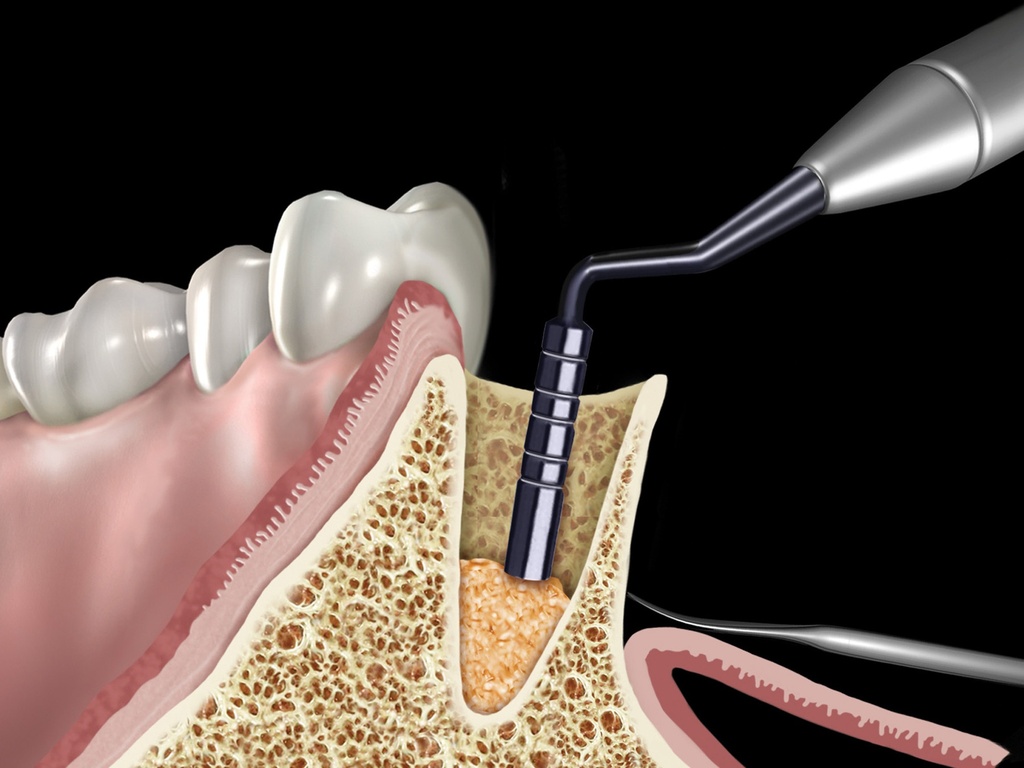

Condenseur d'os Grisdale 8-10-13-15-18 - Hu-Friedy - Delynov

Classe I -

Indications et Contre-indications - Usage Prévu et Avertissements

fabricant : Hu-friedy 3232 N. Rockwell St. Chicago, Il 60618 USA . Réservé aux professionnels de santé. Lire attentivement la notice avant utilisation.